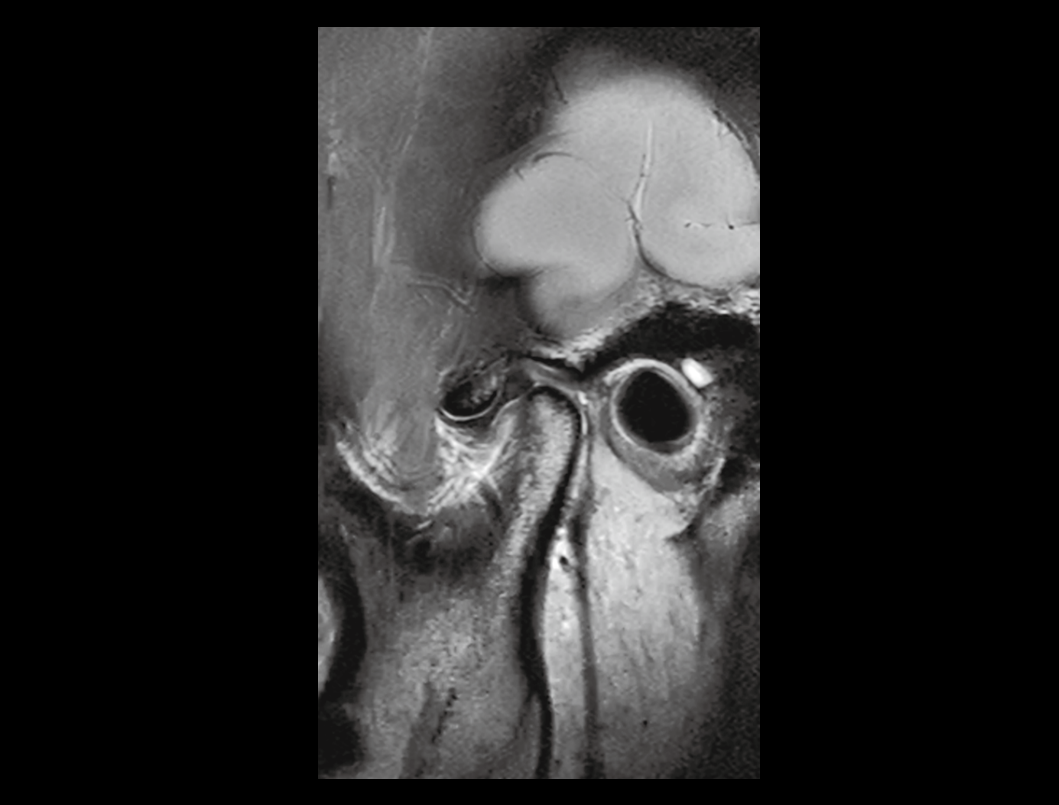

32/48 kanałów RF doskonale uzupełnia nasze zintegrowane cewki o dużej gęstości, dając znaczny wzrost stosunku sygnału do szumu obrazu.